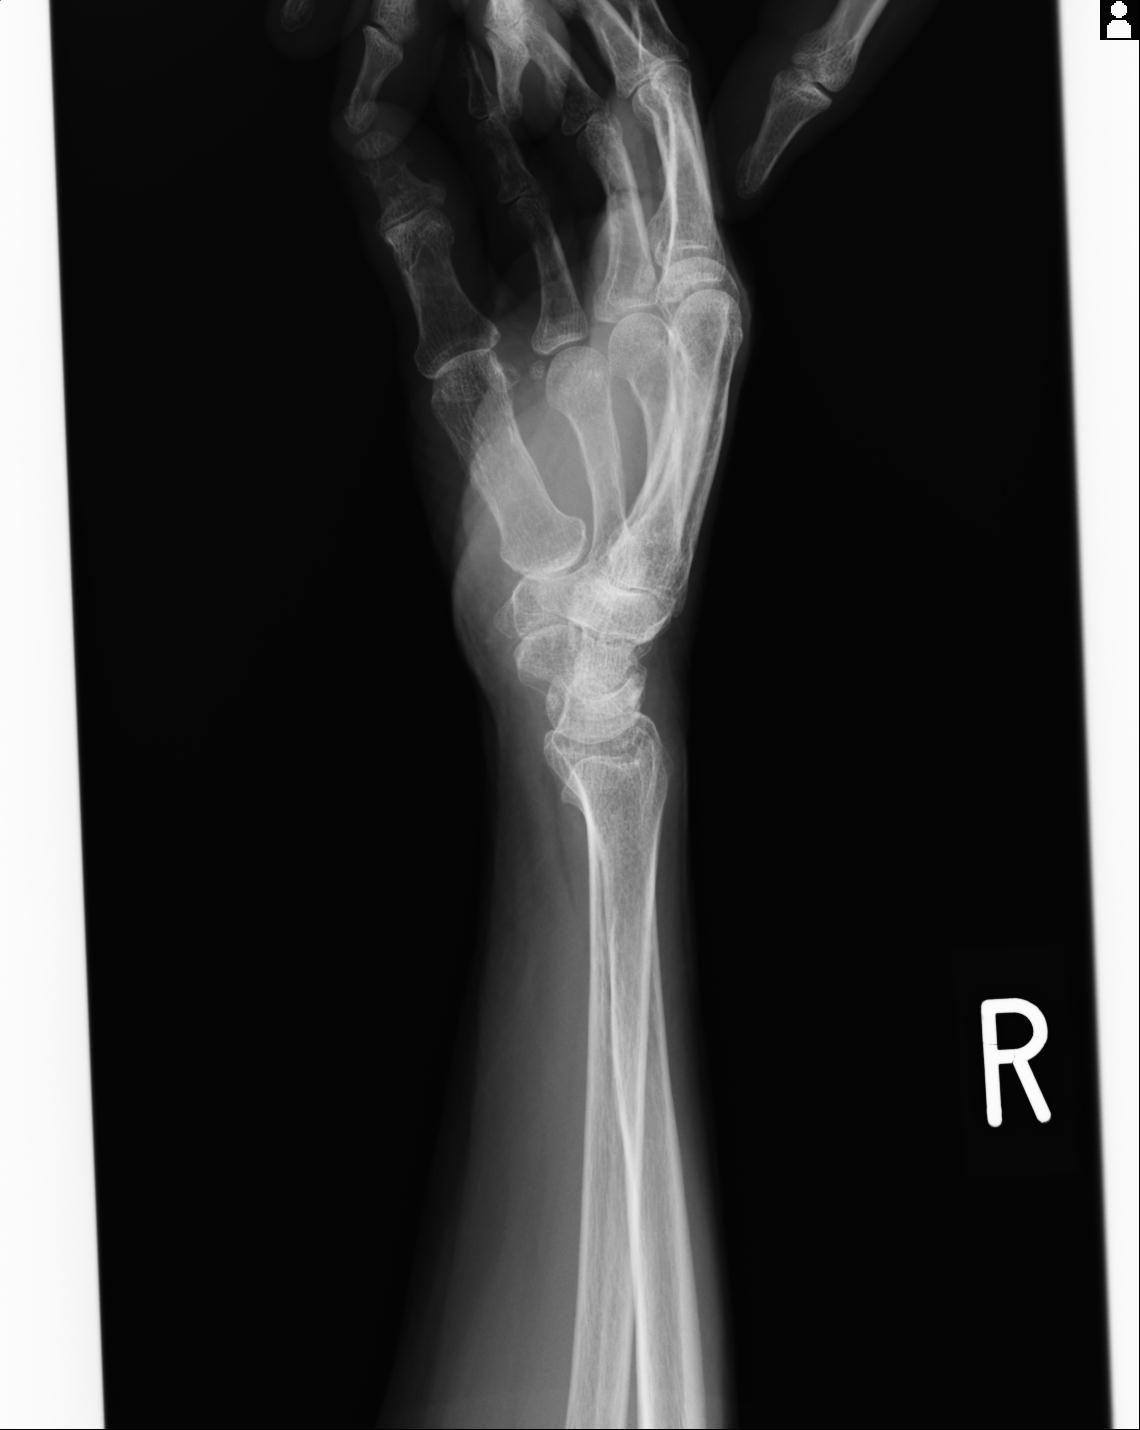

102766 1/5 1/12 左手関節 4R 28歳男性 左橈骨遠位端

102739 12/30 1/5 左手関節 4R 92歳女性 橈骨遠位端